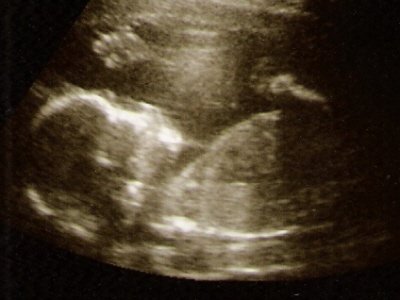

És íme két kép róla:

Kép Kép